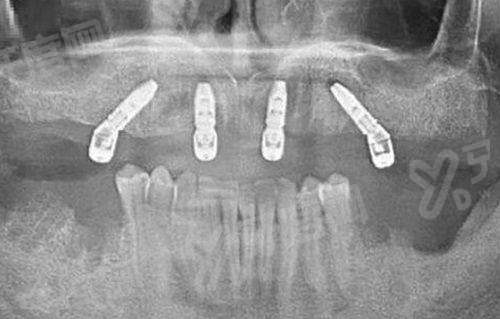

4、种植牙(韩国进口种植体):8000元起/颗(瑞士、瑞典进口的大概1.2万元起,看种植体品牌);